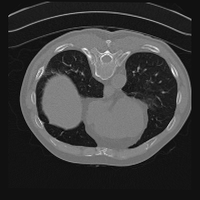

Exp. 3: Adult thorax data: To show the versatility of our approach we also apply it to adult thorax scans. For this experiment no organ specific training is performed but the whole volume is used. We evaluate reconstruction performance similar to Exp. 1 and prediction performance when is projected on an external plane, comparable to X-Ray examination using C-Arms. The latter provides insights about our method’s performance when applied to interventional settings in contrast to motion compensation problems. 60 healthy adult thorax scans were randomly selected, 51 scans used for and nine scans used for . Each scan is intensity normalised and resampled in a volume of with spacing . Using the Fibonacci sampling method, 25 sampling plane of size , evenly spaced between -50 and +50, were rotated over 500 normals. Training took approximately 20 hours for 60 epochs. Fig. 4c shows an example reconstruction result gaining 28dB PSNR with additional SVR. prediction takes approx. 20 ms/slice for this data.

0..5.3 Exp. 3:

We replicated the experiment on adult thorax data without specifically segmented organs. This approach was applied to CT acquisition, shown in Fig 13 and 14, as well as Digitally Reconstructed Radiographs generated using Siddon-Jacobs Ray Tracing shown in Fig. 16.